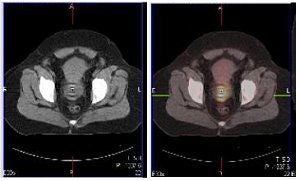

| Above and below, representative images of a 39-year-old patient, currently undergoing treatment, with FIGO stage IB2 squamous cell carcinoma of the cervix. Pretreatment FDG-PET/CT identified an FDG-avid cervical tumor mass plus bilateral iliac and right common iliac metastatic lymphadenopathy. Images courtesy of Dr. Julie Schwarz, Ph.D. |

Twenty-five patients with advanced-stage cervical cancer were included, all of whom were treated with chemoradiation. Whole-body FDG-PET scans were done and co-registered with CT scans. Twenty-eight pretreatment tumor biopsies were done, and pathologic review confirmed the presence of invasive cancer in 26 of 28 cases.